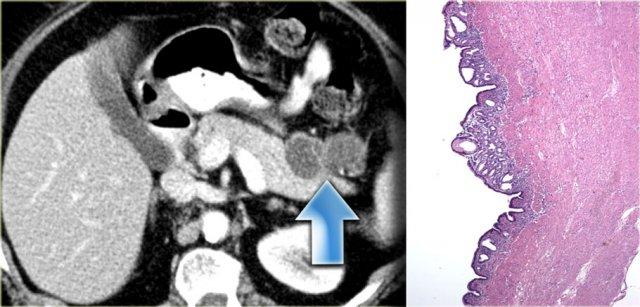

Nang Ruột Đôi

Nang ruột đôi là nang có thành bao gồm đủ ba lớp của thành ruột, bao gồm lớp niêm mạc, lớp dưới niêm mạc và lớp cơ niêm.

Mặc dù chúng ta thường nghĩ đến nang ruột đôi khi thấy một khối dạng nang kề cận ruột, cần nhận thức rằng đây là những tổn thương hiếm gặp.

Chúng có thể xuất hiện ở bất kỳ vị trí nào trong mạc treo, có thể kề cận hoặc cách xa ruột.

Bên trái là hình ảnh nang ruột đôi.

Nang nằm trong mạc treo đại tràng ngang.

Bệnh nhân này ban đầu được nghi ngờ có khối u tụy dạng nang.

Bệnh phẩm cho thấy đầy đủ các lớp thành ruột.